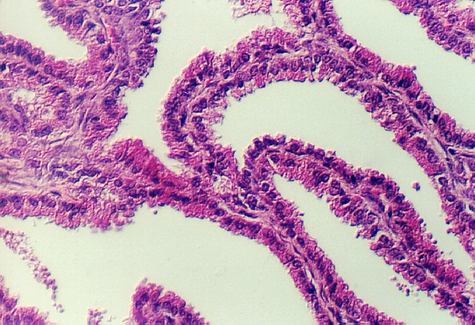

The lumen of this gland is thrown into many folds that appear to branch. This creates a labyrinth of channels, tubes, and pockets into which the secretory product flows. The epithelium shown in the photos below may be simple columnar with patches of pseudostratified epithelium. The appearance of the epithelium is variable and dependent on age and the level of androgen production. One can see some lipochrome pigment in the epithelium, which is present in elderly males. Look at the wall of the gland and again, there are numerous bundles of smooth muscle.

What does the seminal vesicle contribute to the semen?